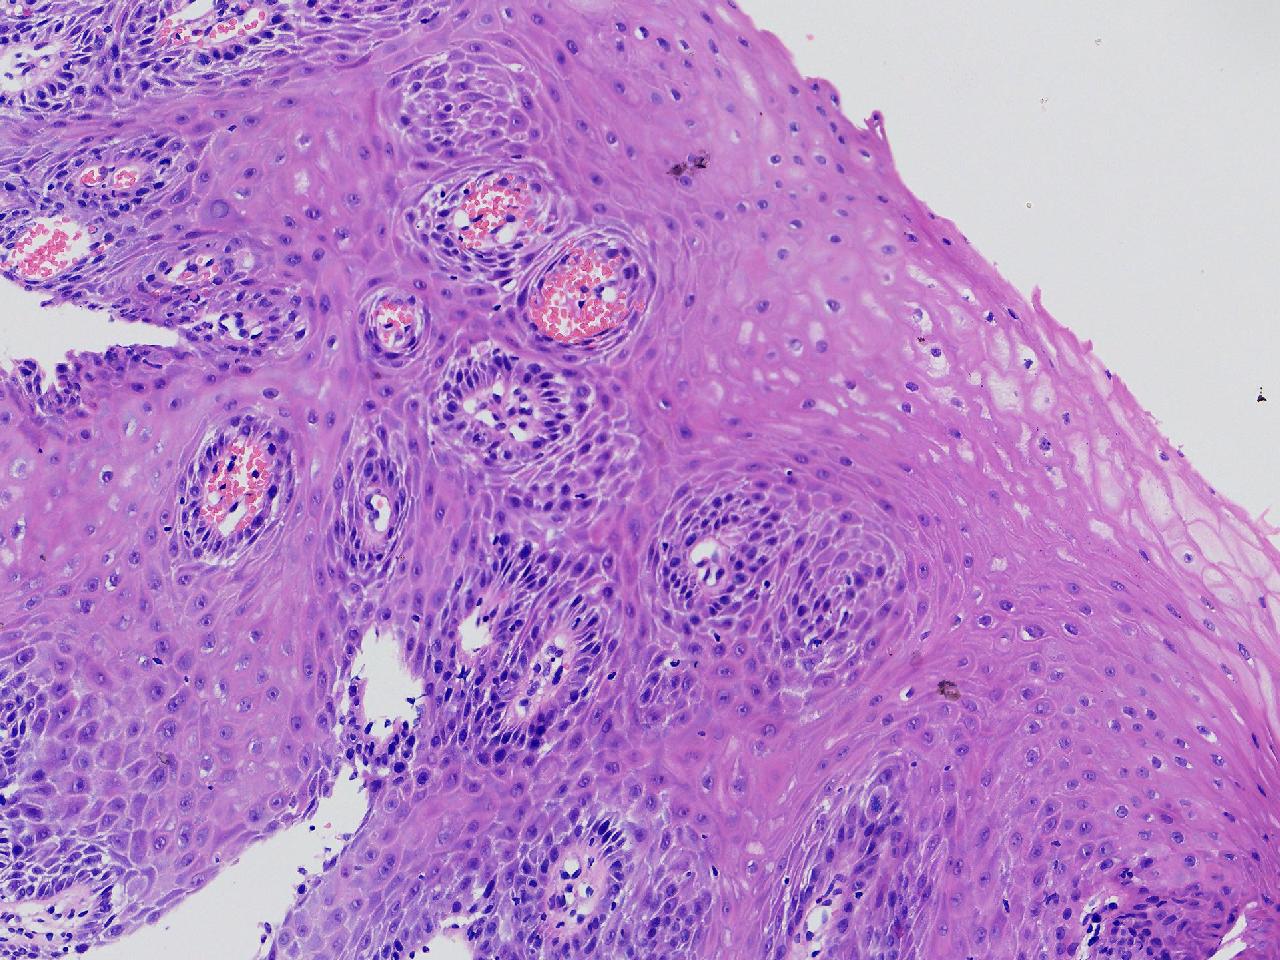

男,62岁,贲门口齿状线上见条状糜烂,活检1块,质软。

贲门口活检

灰白色不整形软组织1块,直径0.2厘米。

鳞皮乳头状增生伴慢性炎。